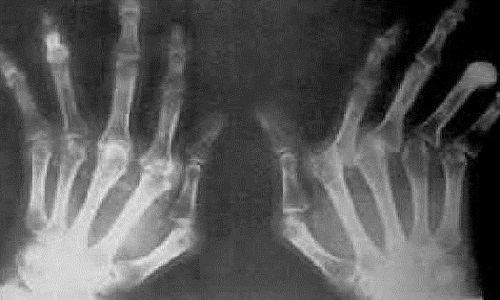

1.骨关节症状 妇女任何年龄均可发病,但常见于更年期。任何周围关节均可被侵犯,而以腕、手指、肘和踝等关节受累最多。游走性和时愈时发的倾向非常显著,精神刺激、贫血和一般体质不健康等,均能加重关节炎的症状老年妇女患此病时,其受累关节,多数为掌指关节和腕关节掌指关节屈曲挛缩,并向尺侧偏,腕关节活动多受限制,背伸功能可能完全消失。关节周围的软组织,有慢性肿胀,关节活动范围减少,局部疼痛时轻时重患者感情有波动或轻度劳累,或偶尔有着凉时,亦可加重局部症状。可能延长数年或数十年。在此期间,病理变化继续在发展,产生结构的破坏或畸形。

在掌指关节屈曲挛缩时,可能延长数年或数十年。如病理变化继续发展,掌指关节可出现结构性破坏或畸形。其他还可并发高血压、阵发性心动过速或过缓失眠等,糖尿病发生率也增加。

2.影像学检查

X线检查特点为非对称关节间隙变窄、软骨下骨硬化和囊性变、关节边缘的骨质增生和骨赘形成、关节内游离体、关节变形及半脱位。磁共振成像(MRI)检查可观察关节内及其周围细微结构,提高骨关节炎的早期诊断率。